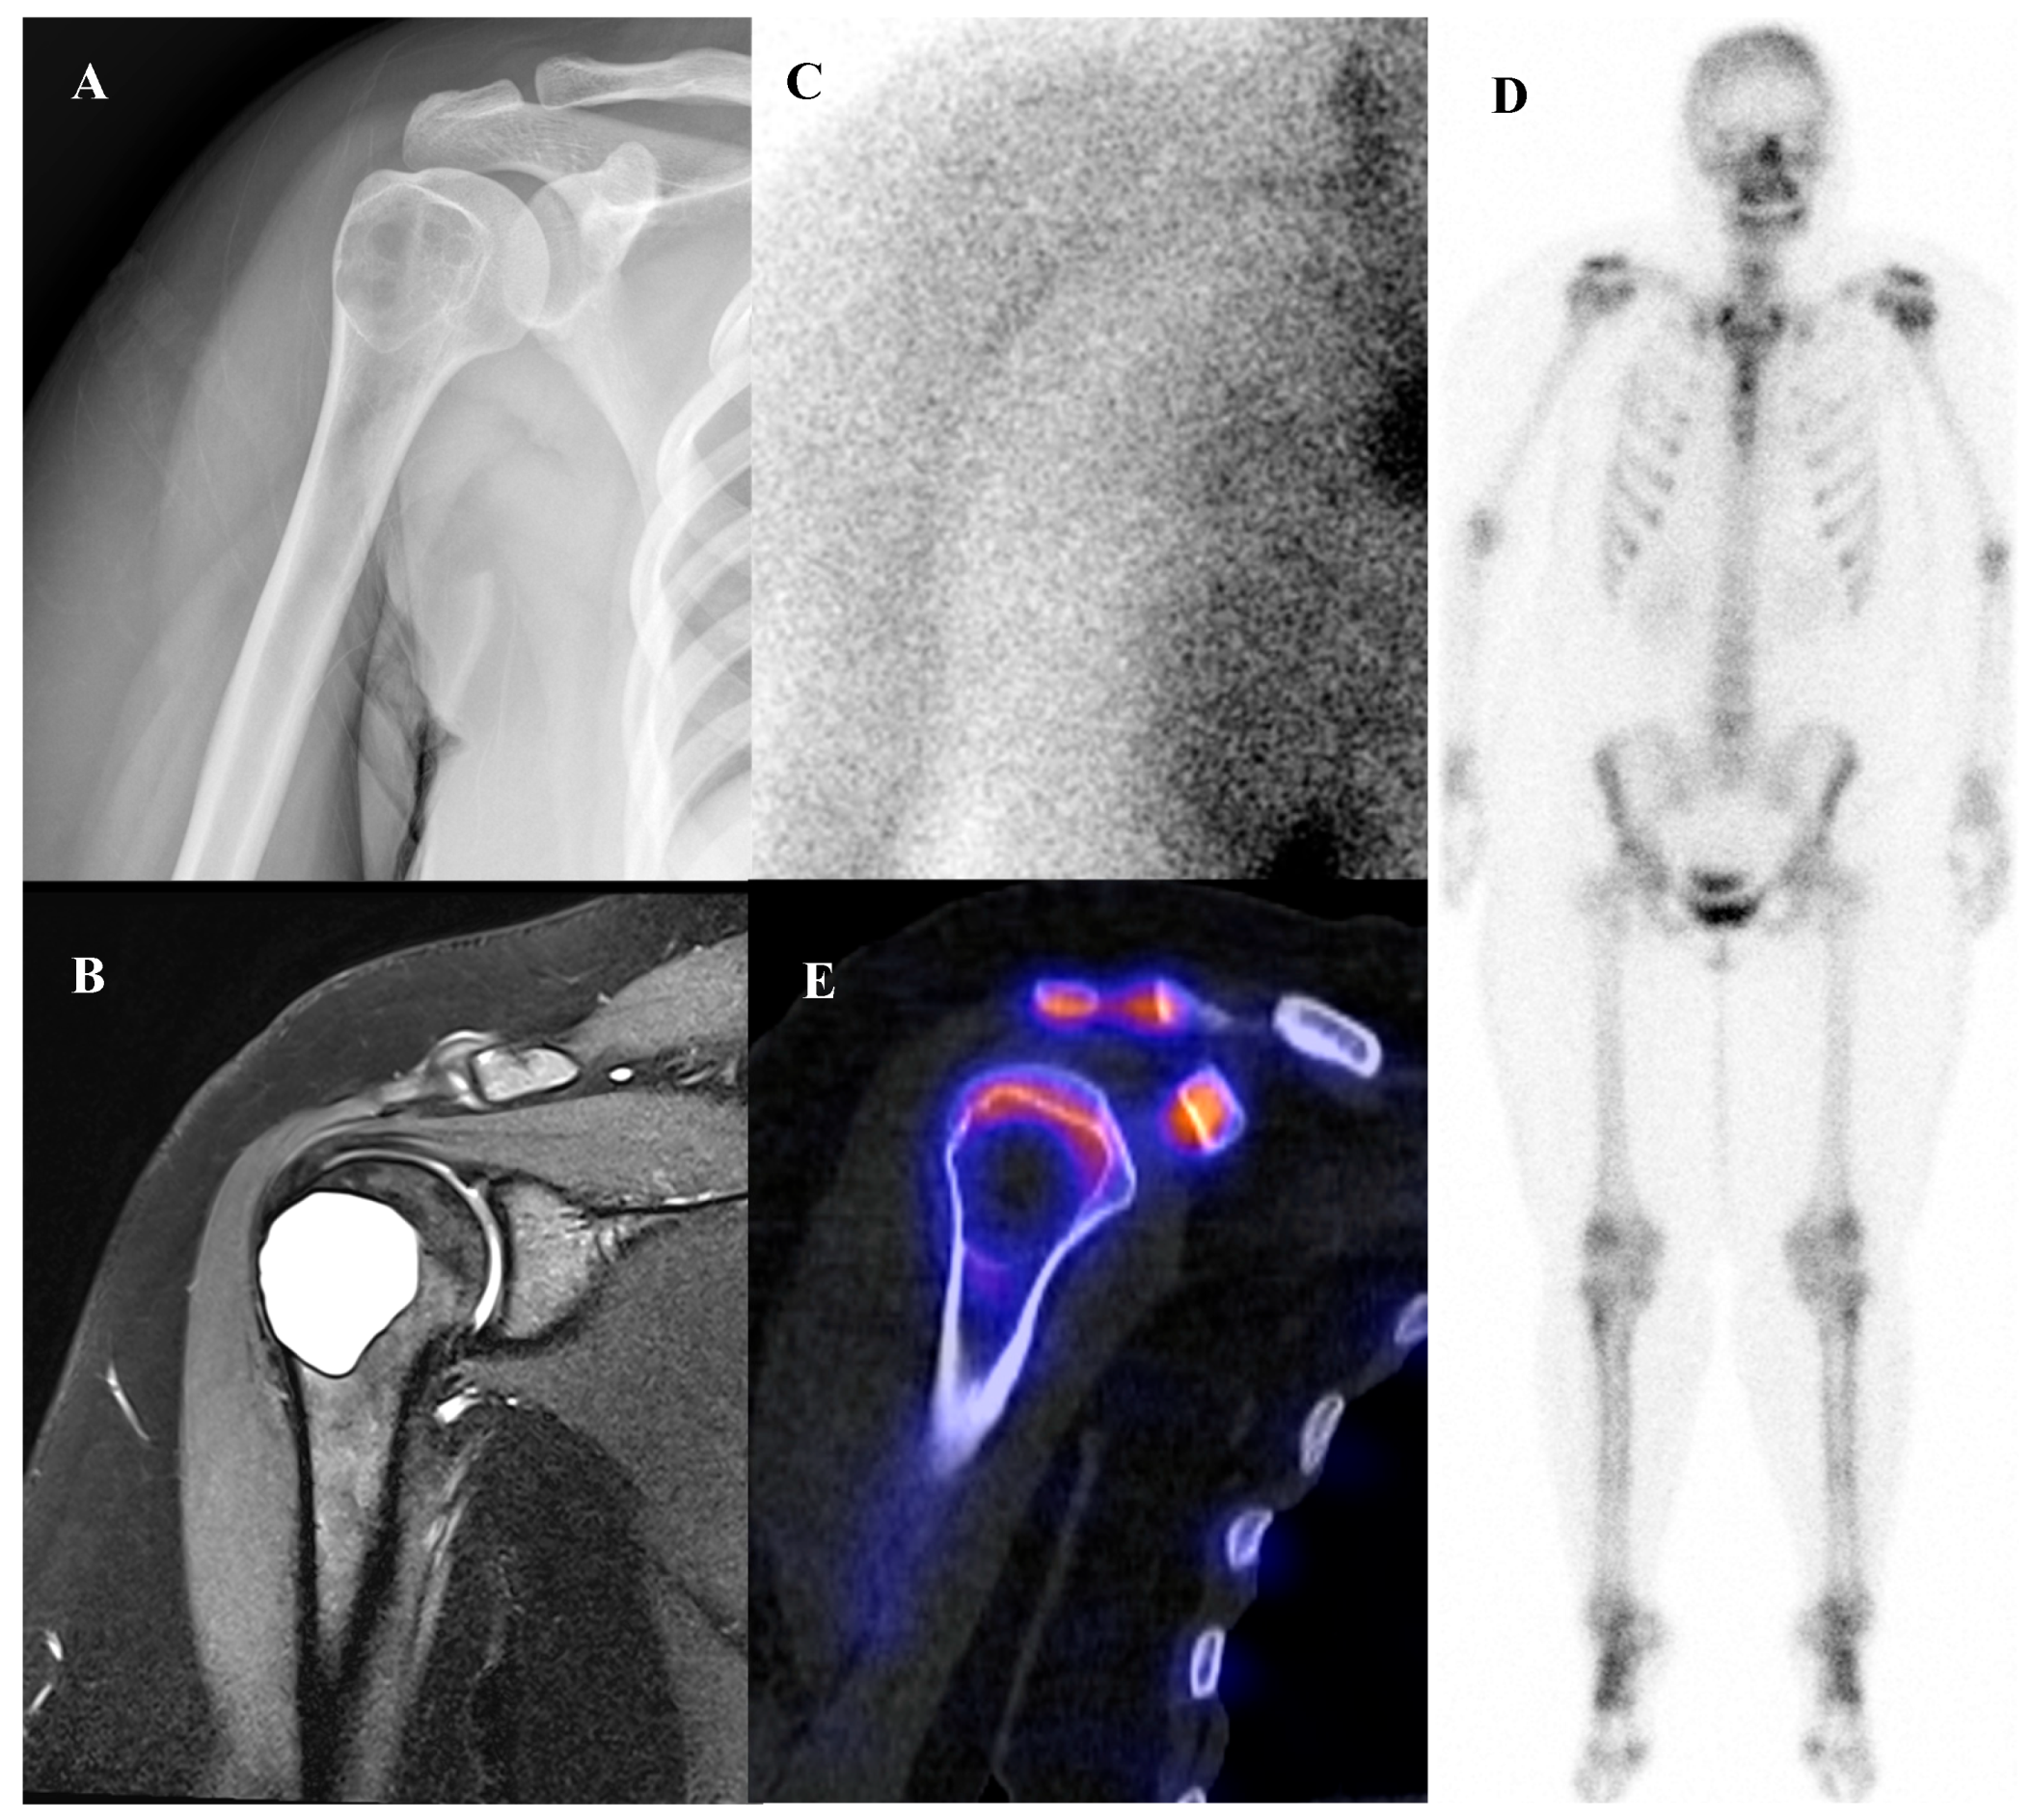

Osteochondroma is the most common benign bone tumor, typically arising in the metaphyses of long bones and most frequently diagnosed in patients younger than 20 years [2]. On bone scintigraphy, the osseous portion of an osteochondroma accumulates tracer. Particularly intense tracer uptake is observed at the bone–cartilage junction of osteochondromas where active endochondral ossification is taking place [72]. The primary role of nuclear medicine is in the surveillance for malignant transformation to a secondary chondrosarcoma, a rare but serious complication. A sudden, marked, and heterogeneous increase in tracer uptake in a previously stable osteochondroma, particularly in an adult, is highly suspicious for malignant change [73]. [18F]FDG PET/CT is superior to bone scintigraphy for this purpose, as a significant increase in SUVmax provides a more specific and quantifiable marker of malignant transformation than a general increase in osteoblastic activity. Osteochondromas generally show no or faint [18F]FDG uptake, with approximately one-third of patients showing uptake higher than that of the background [54,64,74]. Figure 6 illustrates a typical case of scapular osteochondroma, in which MRI, bone scintigraphy, and SPECT/CT demonstrated the characteristic features of this lesion.

Figure 6.

A 16-year-old female with osteochondroma of the right scapula. (A) Plain radiograph shows a protruding mixed sclerotic mass at the scapular cap. (B) T2-weighted fat-suppressed magnetic resonance imaging demonstrates a pedunculated, lobulated osseous lesion arising from the scapular cap, with continuity of the cortex and medulla and a thin, T2-bright enhancing cartilaginous cap. (C) Bone scintigraphy shows focal uptake at the lesion site. (D,E) Bone single-photon emission tomography/computed tomography demonstrates focal tracer uptake at the bone–cartilage junction.